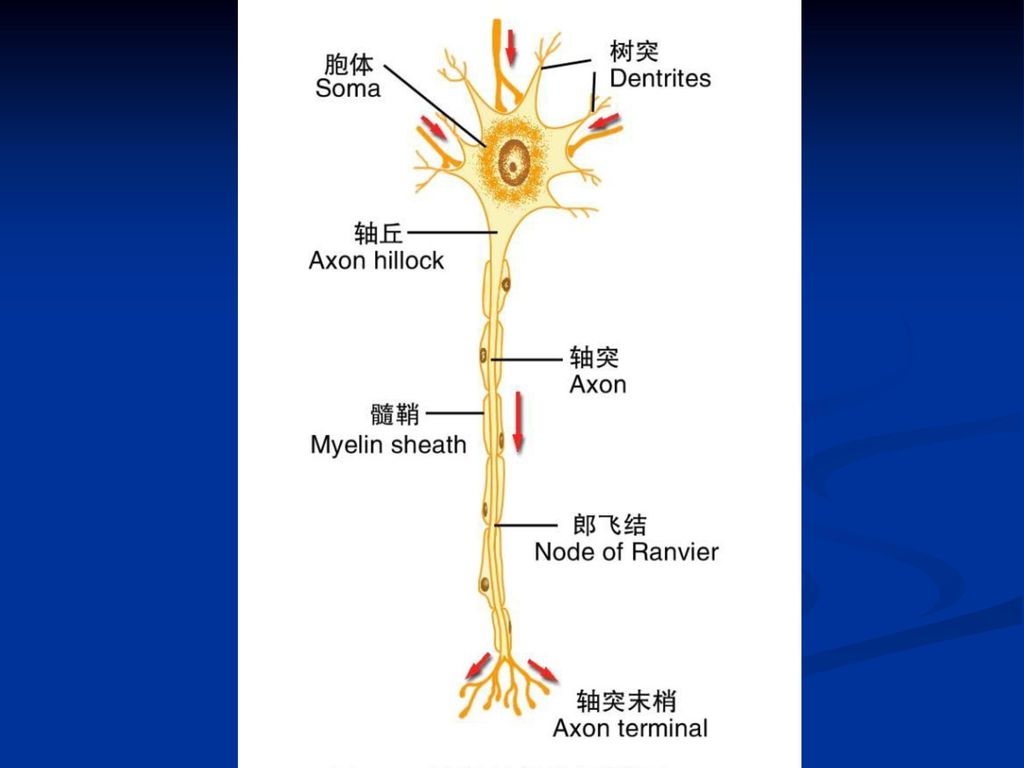

神经纤维

高二生物教案:神经纤维图示

功能:接受刺激和传递信息 突触 神经纤维 胞体 树突 : 较短,一